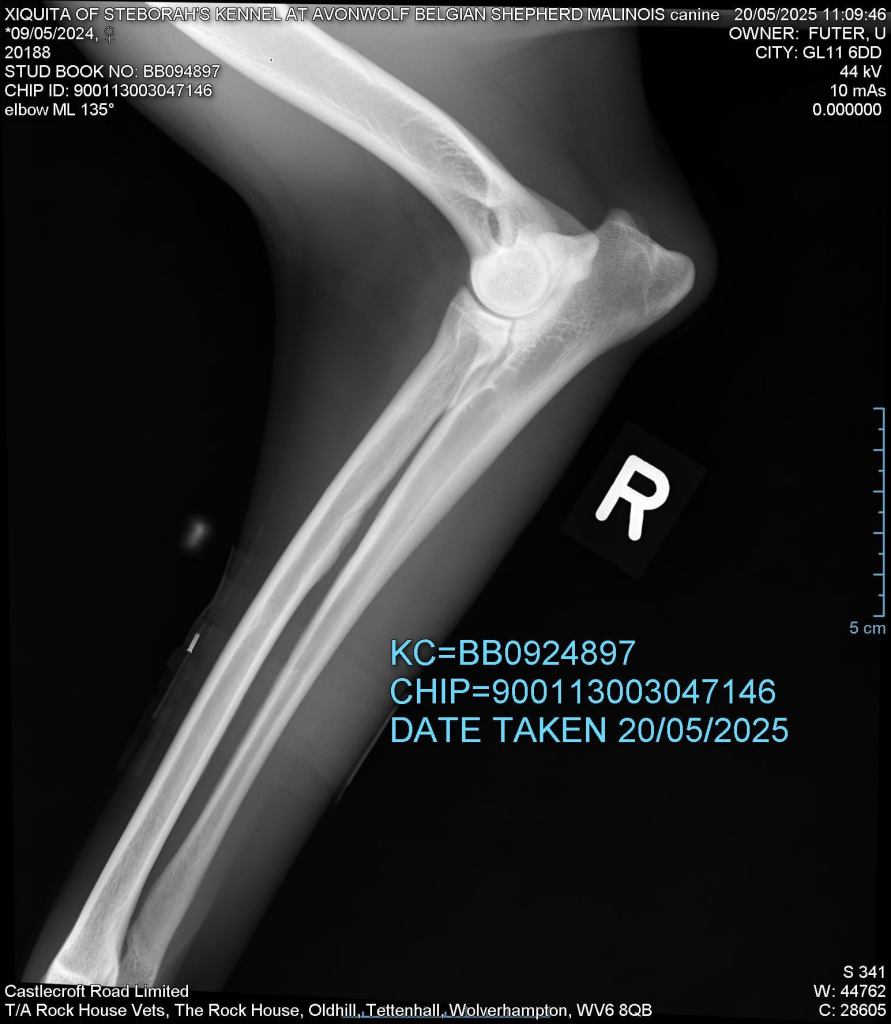

Elbows 0/0